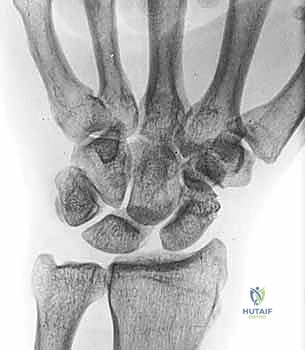

FIG 2 • A. Clenched-fist PA view with the wrist in supination, demonstrating a significant increase in the scapholunate interval space.